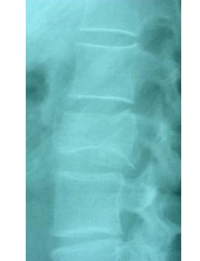

Estabilització percutània de fractures vertebrals inestables

En casos de fractures vertebrals complexes, inestables, comminutes, etc. es requereix una estabilització addicional de la fractura mitjançant una artròdesi percutània, i en alguns casos en els quals hi ha compromís neurològic, una descompressió del canal medul·lar. L’artrodesi percutània permet estabilitzar l’estructura compromesa de la columna vertebral i descarregar la càrrega del pacient sobre la fractura. Addicionalment se solen cementar les vertebres artròdesis i la fractura vertebral mitjançant cifoplastia.